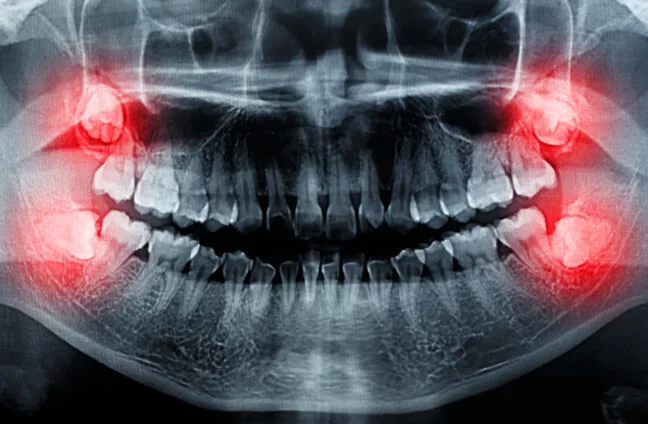

Our mouths can’t handle wisdom teeth due to a lack of space, leading to impaction. Wisdom teeth can develop sideways and damage surrounding teeth if they do not have enough room to grow. Tooth impaction and crowding can be excruciatingly painful. When this appears on X-rays, wisdom tooth extraction is recommended. Our dentists can assist you with this sort of extraction.

Types of Wisdom Teeth Impaction

- Mesial Impaction: Appears at an angle toward the next tooth (second molar).

- Vertical Impaction: Teeth that appear straight up or down like other teeth but stay trapped within the jawbone.

- Horizontal Impaction: It appears perpendicular to the other teeth as if the wisdom tooth is sideways within the jawbone.

- Distal Impaction: Appears at an angle toward the back of the mouth.